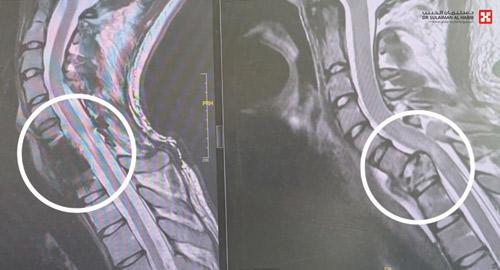

وقد أظهرت الأشعة وجود كسر مركب بالفقرة العنقية رقم «7»، وانزلاق غضروفي حاد وضغط على النخاع الشوكي، مع شلل في الأطراف العلوية ابتداءً من العصب رقم «7» وإلى الأسفل. وقد أجريت له عمليتان؛ تم في الأولى إزالة الفقرة العنقية السابعة المتهشمة بالكامل، والاستعاضة عنها بأخرى صناعية وتثبيتها بصفيحة وبراغي، في تدخل طبي نادر حيث تم الدخول من الجهة الأمامية، واستمرت العملية لـ«5» ساعات، وأعيد إلى العناية المركزة ووضع على التنفس الاصطناعي .